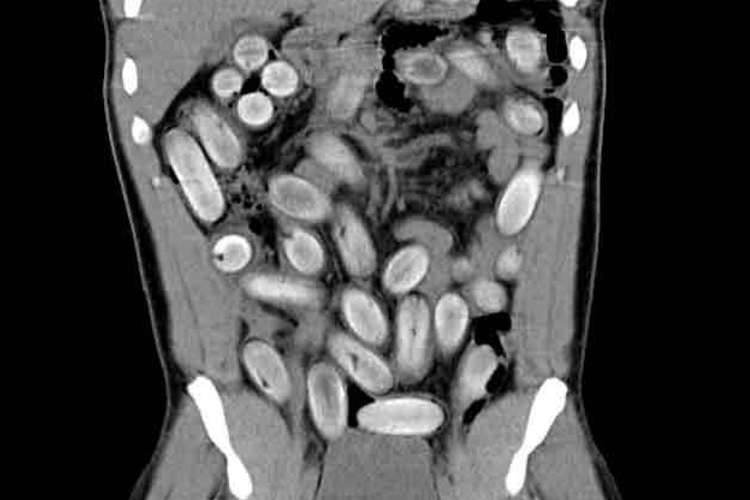

É um exame que utiliza aparelhos computadorizados que emitem radiação (Raio-X) para obter imagens de órgãos internos.